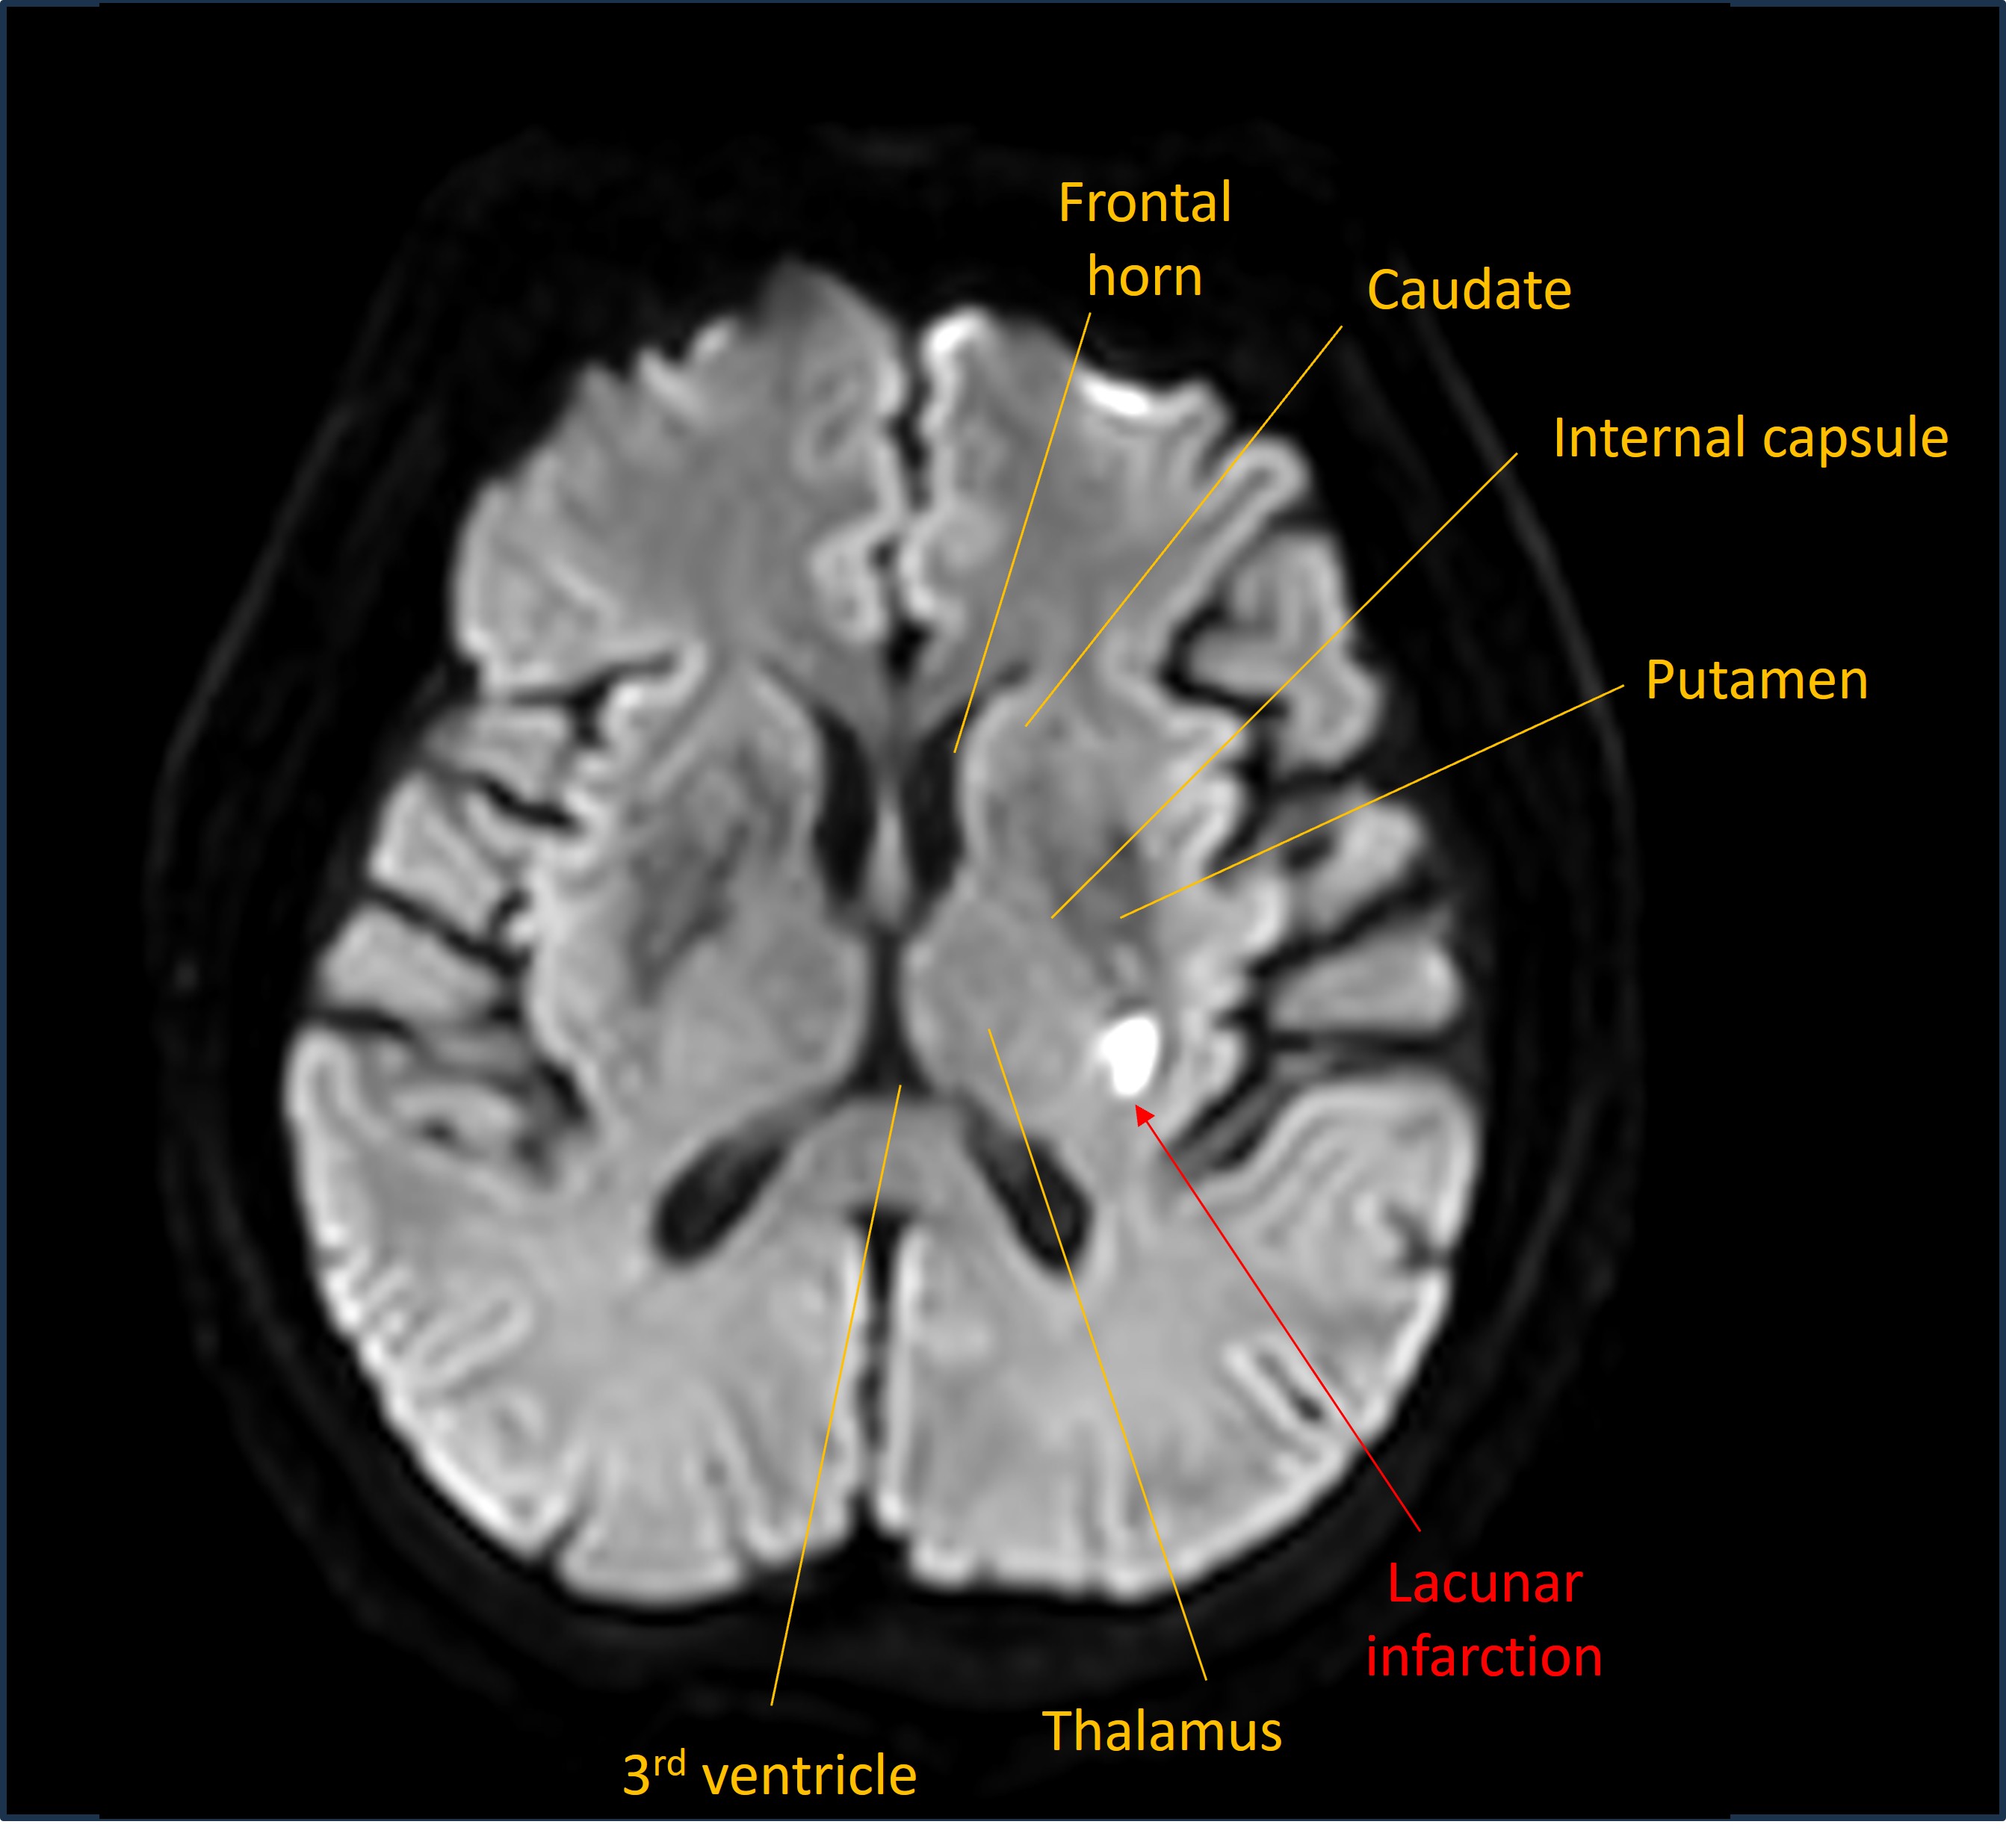

An MRI was then performed. This revealed an acute diffusion-restricting lesion in the posterior limb of the internal capsule - consistent with a lacunar stroke in the territory perfused by the small perforating arteries.

MRI